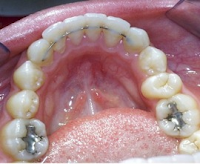

A Fixed retainer, or permanent retainer is a different type of retainer than the 2 above. A fixed retainer typically consists of a passive wire bonded to the tongue-side of the teeth (usually on the Lower teeth only, depending on the bite). Unlike the previously-mentioned retainer types, fixed retainers cannot be removed by the patient. Some doctors prescribe fixed retainers regularly, especially where active orthodontic treatments have effected great changes in the bite and there is a high risk for reversal of these changes. This retainer is often kept in place for life. Fixed retainers may lead to tartar build-up or gingivitis due to the difficulty of flossing while wearing these retainers. As with dental braces, patients often must use floss threaders to pass dental floss through the small space between the retainer and the teeth. We will help you understand how to take care of this retainer!!